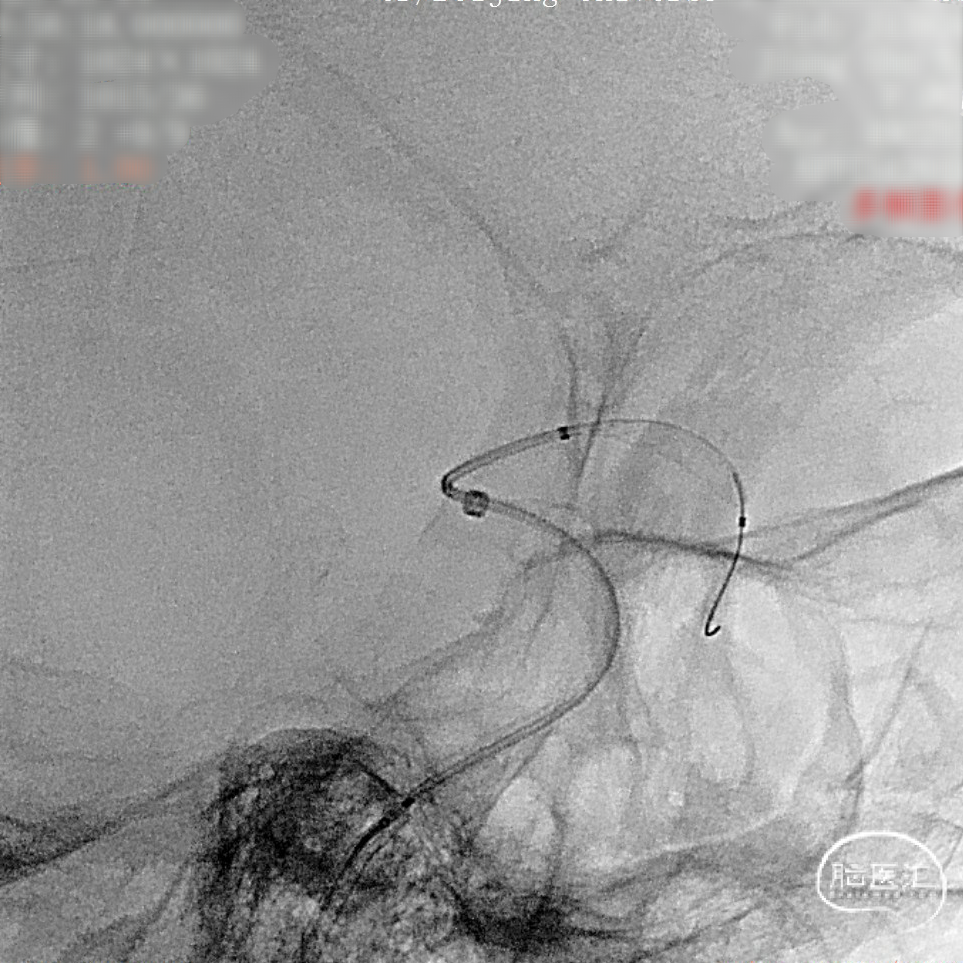

微导管到位后释放支架头端。

头端完全打开,锚定。

完全覆盖动脉瘤颈后拟过弯。

支架完全释放。